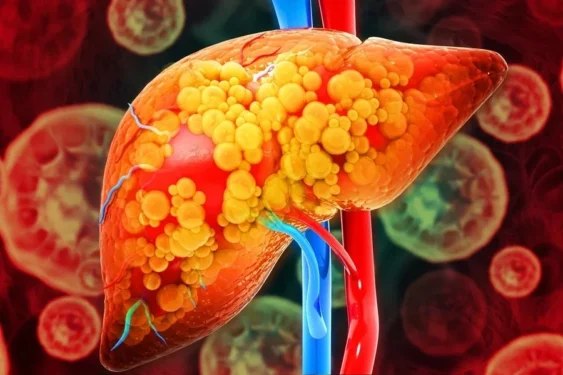

Ainda que ocasional, o consumo excessivo de álcool (mais de quatro doses em um dia para mulheres e cinco para homens) é bastante prejudicial para o fígado. Uma nova pesquisa da Universidade do Sul da Califórnia, nos Estados Unidos, mostra que pessoas com gordura no fígado podem ter três vezes mais risco de desenvolver fibrose no órgão se beberem muito pelo menos uma vez por mês.

A pesquisa foi publicada nesta quinta (2/4) na revista científica Clinical Gastroenterology and Hepatology. Os cientistas descobriram que beber muito em um dia só é mais prejudicial do que dividir a mesma quantidade de álcool em vários dias.

“O estudo é um grande alerta porque, tradicionalmente, os médicos tendem a observar o total de álcool consumido, e não como ele é consumido, ao definir o risco hepático. Nossa pesquisa sugere que o público deve estar atento do perigo de beber muito, mesmo ocasionalmente, e que deve evitar mesmo se consumir álcool moderadamente no resto do tempo”, afirma o hepatologista Brian P.Lee, o principal autor do estudo, em comunicado.

A pesquisa foi feita analisando dados de um levantamento nutricional de longo prazo da população americana e incluiu informações de 8 mil adultos coletadas entre 2017 e 2023. Os cientistas observaram principalmente a relação entre o exagero na bebida ocasional e a fibrose hepática avançada.

Exagero na bebida é comum

Mais de metade dos participantes afirmou beber excessivamente de vez em quando e 16% dos pacientes com gordura no fígado disse exagerar ocasionalmente. Os resultados foram comparados entre pessoas da mesma idade e sexo.

Lee acredita que beber grandes quantidades de álcool de uma vez pode sobrecarregar o fígado e aumentar a inflamação, o que causa cicatrização e danos ao órgão. Pessoas que têm esteatose hepática estão ainda mais em risco pois o fígado já está lidando com a gordura além dos problemas causados pelo álcool.

“Apesar de o estudo ter sido focado em pacientes com gordura no fígado, os achados são pertinentes para uma população maior de pacientes. Mais de metade dos adultos disse beber muito ocasionalmente, e este assunto merece mais atenção de médicos e pesquisadores para entender melhor, prevenir e tratar doenças hepáticas”, afirma o pesquisador.